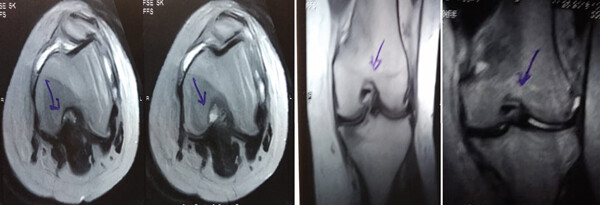

MRI:治療前后的MRI結(jié)果

治療前 MRI 顯示內(nèi)側(cè)和外側(cè)半月板后角 III 級(jí)撕裂。

治療后MRI檢查顯示內(nèi)側(cè)和外側(cè)半月板后角撕裂有所改善。患者癥狀改善,日常生活活動(dòng)能力增強(qiáng)。

結(jié)論:間充質(zhì)干細(xì)胞治療后,MRI檢查顯示內(nèi)側(cè)和外側(cè)半月板后角撕裂有所改善 ,關(guān)節(jié)功能也有改善,未出現(xiàn)嚴(yán)重不良事件。可以達(dá)到干細(xì)胞治療半月板損傷短期療效的目標(biāo)。